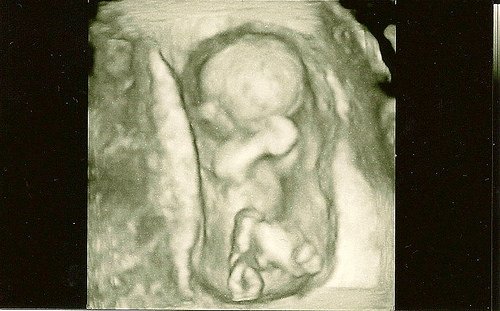

каквото Бог даде,важното е да са здравички.

каквото Бог даде,важното е да са здравички.

А това в коя седмица се случва ?Кога се оформя ?

А това в коя седмица се случва ?Кога се оформя ?